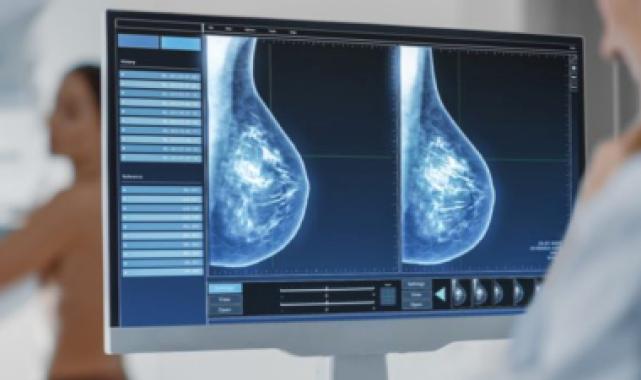

Dr. Güler, meme kanserinin erken teşhis ile tedavi edilebilecek bir hastalık olduğunu belirterek, 50 yaş üzeri kadınların her yıl mamografi yaptırmasının önemine dikkat çekti. Güler, “Kötü haber alırım korkusu nedeniyle mamografi taramalarına girmeyen kadınlarımız var. Bu korkuyu aşarak erken tanı ile hayatlarınızı kurtarabilirsiniz. 40-50 yaş arasındaki kadınlar da doktorlarına danışarak mamografi sıklığını belirlemelidir. Unutulmamalıdır ki erken teşhis hayat kurtarır” diye konuştu.